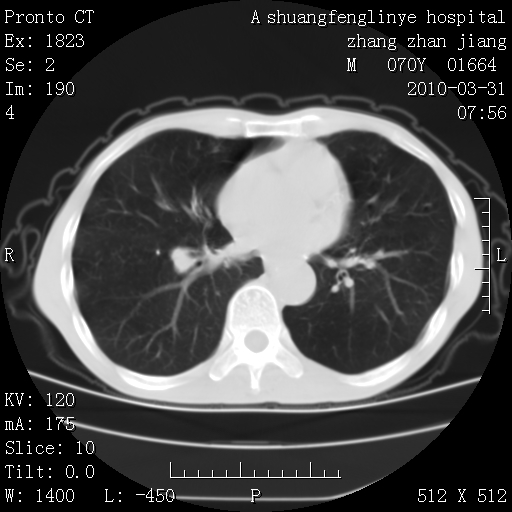

双上肺继发型tb并左上空洞形成,主动脉冠脉钙化。

支持:继发性肺结核伴空洞形成!建议纤支镜检查待出外周围型肺癌可能!

1)两肺上叶继发性肺结核并左肺上叶空洞形成。2)冠状动脉及主动脉钙化。